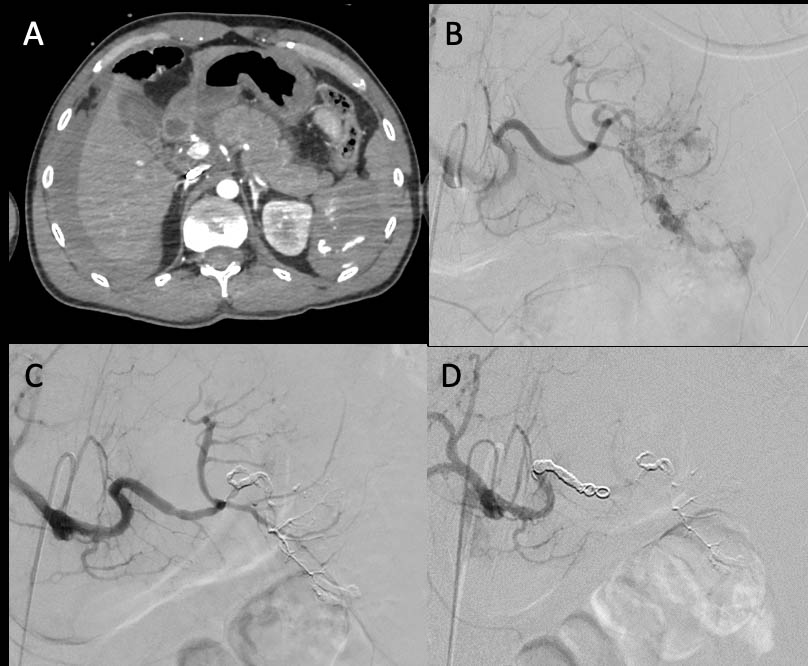

Sequence of technical steps during the embolization procedure. (A ...